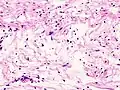

| Micrograph of a schwannoma showing both a cellular Antoni A area (top) and a loose paucicellular Antoni B area (bottom). HE stain. | |

Antoni A area of schwannoma with Verocay bodies (one annotated by circle) -